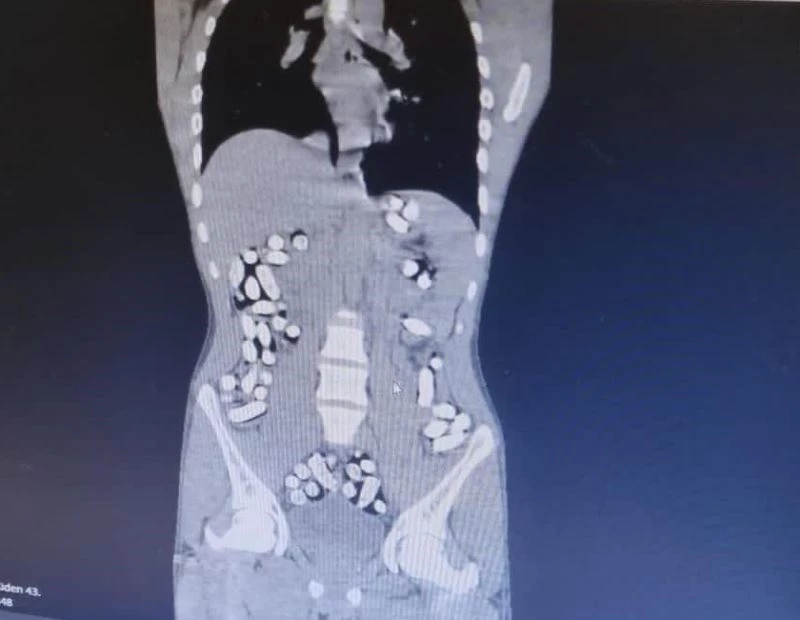

Erzurum’da polis ekipleri tarafından İran’dan gelen yolcu otobüsünde ve bir araçta yapılan aramada şüpheli hareketlerde bulunan 5 kişi gözaltına alındı. Kontrol amaçlı hastaneye götürülen şahısların yapılan incelemede toplam 6 kilo 145 gram afyon sakızı ve 709,83 gram eroin yuttukları tespit edildi.

Erzurum Emniyet Müdürlüğü Narkotik Suçlarla Mücadele Şube Müdürlüğü ekipleri, batı illerine uyuşturucu madde nakli yapan şahıs ve araçlara yönelik Erzurum-Erzincan karayolu üzerinde yaptıkları denetimlerde İran’dan ülkeye giriş yapan bir yolcu otobüsünü durdurdu. Kontroller esnasında otobüsteki Mehdı B., Mılad F. ve Sıraus G. isimli şahısların hareketlerinden şüphelenen ekipler, şahısları iç beden muayenesi için hastaneye götürdü. Yapılan muayene ve röntgen çekimi sonrasında şahısların uyuşturucu maddeleri kapsül haline getirerek yuttukları tespit edildi. Doğal yollarla şahısların midelerinden çıkarılan 210 kapsül halinde 3 kilo 192,18 gram afyon sakızı ve 62 kapsül 709,83 gram eroin ele geçirildi.

Bir başka olayda, yine Erzurum-Erzincan karayolu üzerinde İran’dan ülkeye giriş yapan bir araç durduruldu. Araçta bulunan Masoud T. ve Soleman O. isimli şahısların şüpheli hareketler sergilemesi ve üzerlerinde tokluk hissi veren ve mide-bağırsak temizleyici ilaçlar bulunması sebebiyle yutmak suretiyle uyuşturucu madde nakli yaptıklarından şüphelenilerek, muayene için hastaneye götürüldü. Şahısların uyuşturucu maddeleri kapsül haline getirerek yuttukları tespit edildi. 411 kapsül halindeki 2 kilo 953 gram afyon sakızı ele geçirildi.